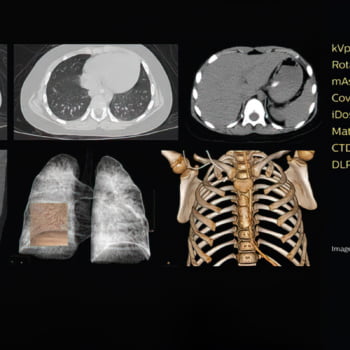

Simplifique o fluxo de trabalho e reduza a variabilidade

A plataforma de fluxo de trabalho inteligente iFlow tem ferramentas automáticas para fluxos de trabalho simples e eficientes. Obtenha uma digitalização excelente com alto rendimento, mantendo os custos operacionais baixos e aproveitando ao máximo os recursos de treinamento.